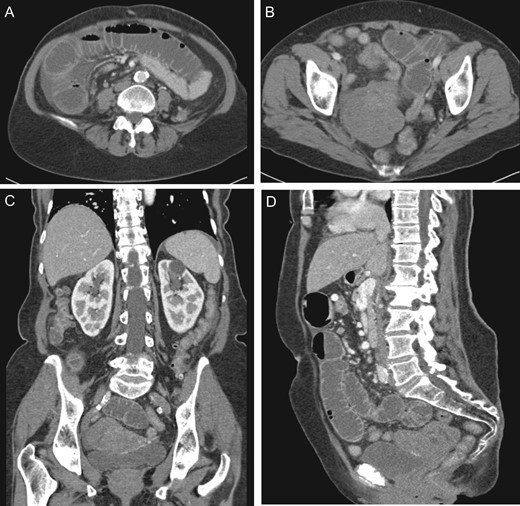

After discussion with gynecology and gynecologic oncology, she underwent an exploratory laparotomy. Upon entry into the abdomen, distended and congested small intestine was visualized without apparent ischemic changes. The small bowel was twisted about the superior mesenteric artery axis (SMA) and tethered toward the pelvis. The small bowel was then eviscerated to reveal a large, pedunculated 9 × 7 × 8 cm3 mass, originating from the antimesenteric side of the small intestine and located 162 cm from the ileocecal valve. The small intestine was noted to have volvulized around this pedunculated mass. It was immediately detorsed and normal peristaltic function returned within minutes. Starting with the decompressed small intestine, the bowel was run from the ileocecal valve to the ligament of Treitz without any other abnormalities noted. A segmental small bowel resection was then performed to include the mass and associated mesentery. A total of 14 cm of bowel was resected (Fig. 3). The remainder of the abdomen was inspected and noted to be free of pathology, particularly the uterus, fallopian tubes and ovaries. Pathology demonstrated evidence of a serosal spindle-cell neoplasm, four mitotic figures/5 mm2 and immunohistochemistry strongly positive for CD117 and DOG1. No lymph node metastasis was identified. These findings were consistent with a low-grade GIST. Patient did well post-operatively and was discharged home on post-operative Day 6.

(A) Eviscerated small intestine with pedunculated mass. (B) Pedunculated mass with forceps indicating site of volvulus resulting in luminal narrowing from compromised blood flow. (C) Small bowel segmental resection.